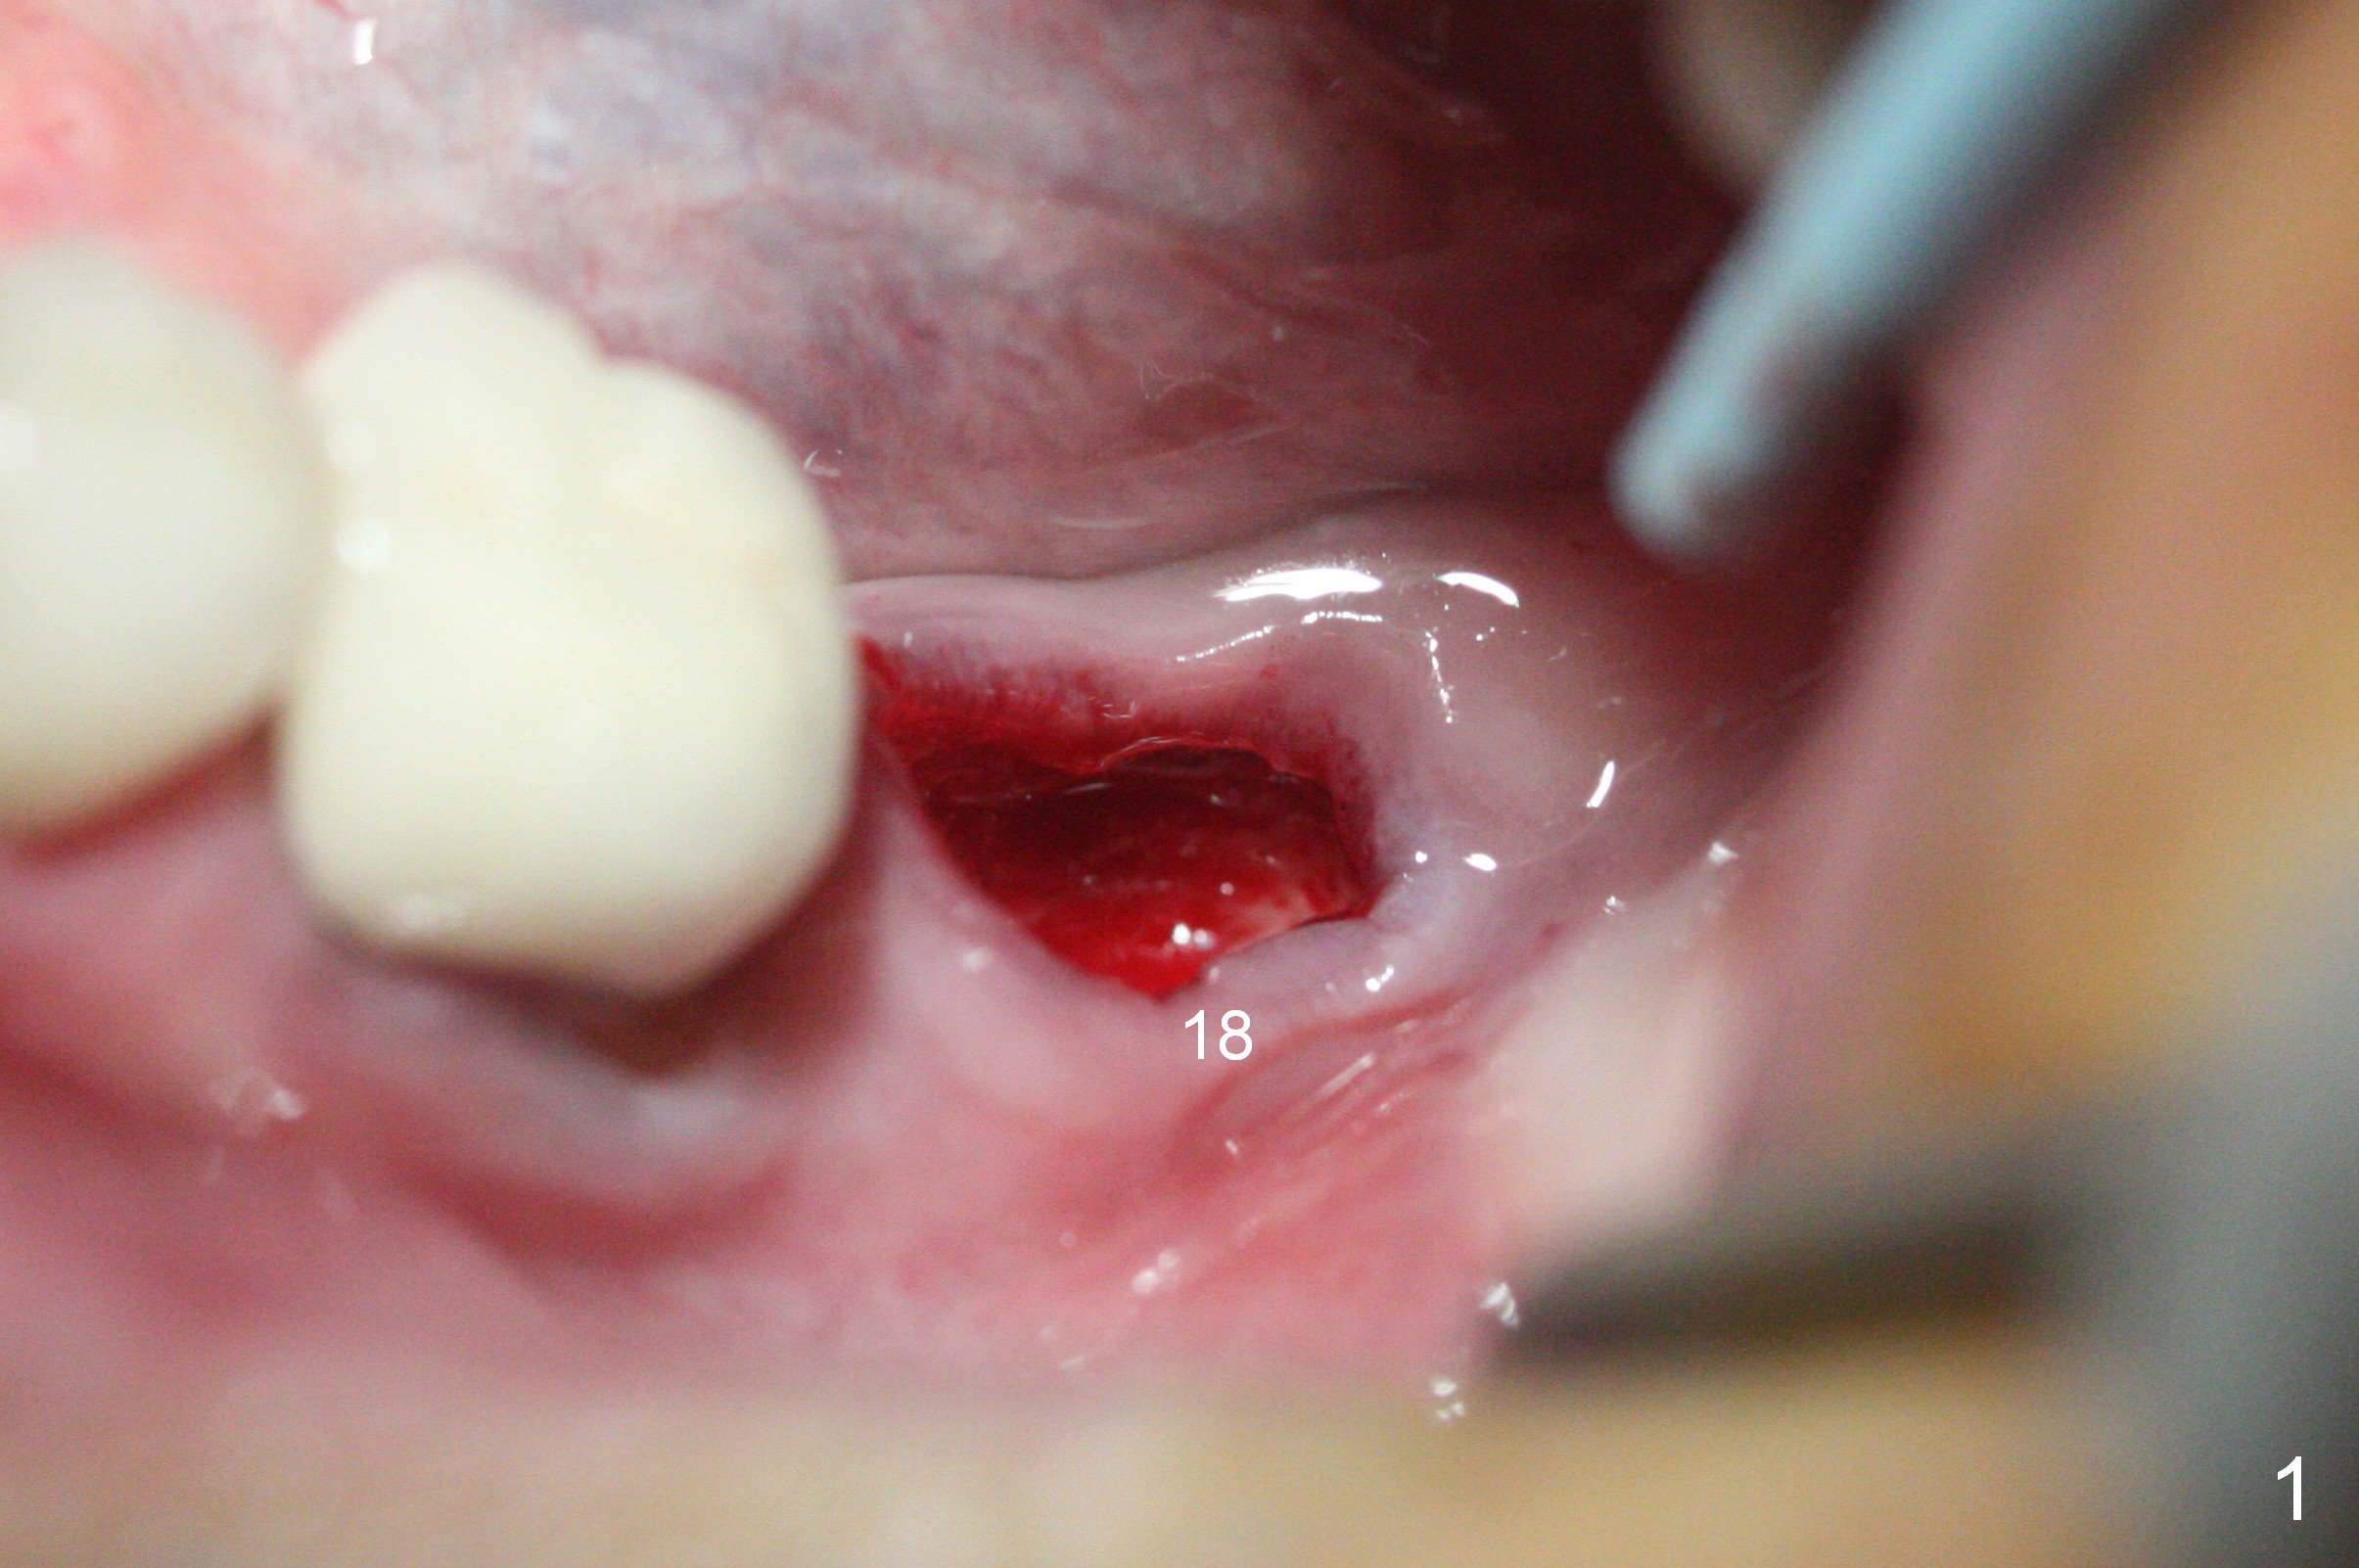

One method to control osteotomy depth for immediate implant is to use the gingival margin. As Fig.1 indicates, the gingival margin is uneven at the site of #18. Since the osteotomy in this case is established mesially, large drills and implants may distort the gingiva so that the gingival margin is an unreliable landmark. Infiltration anesthesia does not produce profound pain control. When the patient reports discomfort during the osteotomy, it may be regarded as violation of the Inferior Alveolar Canal. Therefore osteotomy depth control is quite difficult. With shallow depth and soft bone, implants easily lose stability.